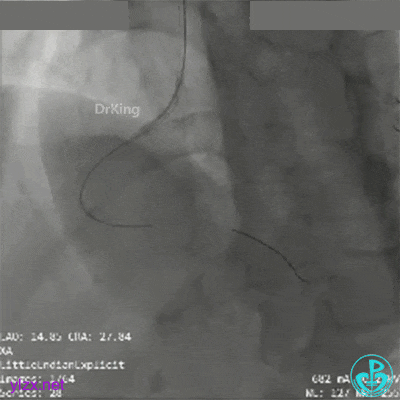

RCA第一转折50%狭窄,第二转折前100%闭塞。

导管、导丝飞走。

导管、导丝重新到位,血栓抽吸后,经抽吸导管注射替罗非班,血栓负荷减少,残余狭窄重。

球囊再次扩张远端后,替罗非班注射,示远端狭窄改善,近端出现什么情况?血栓?夹层?

直接指引导管抽吸,未见血栓。

冒烟显示近端仍然有异物,远端造影剂滞留。

高度怀疑近端夹层。